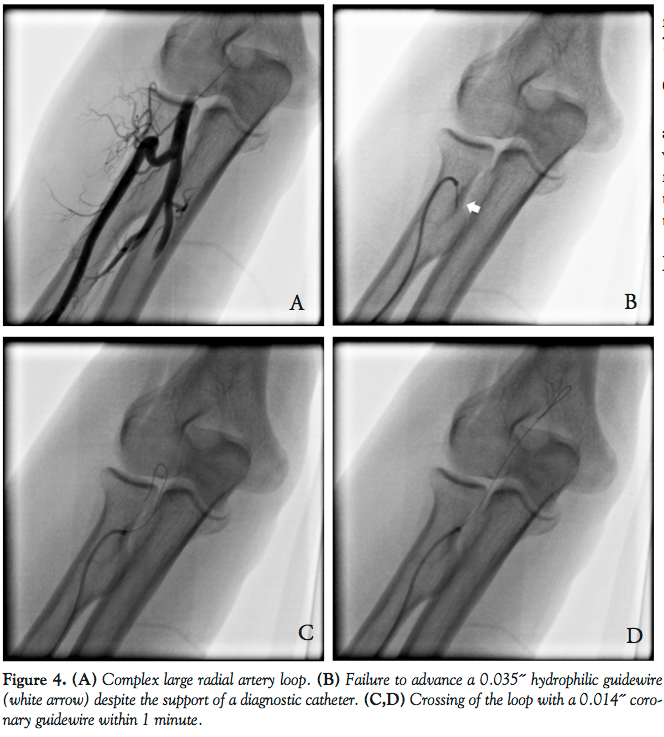

TR procedure and technique description. After local skin anesthesia with 2 cc of lidocaine 2%, the radial artery puncture was performed with a radial cannulation needle and guidewire according to operator expertise. A 4-6 Fr, 11 cm sheath was then inserted and a drug cocktail of verapamil (2 mg) and isosorbide dinitrate (200-400 μg) was injected through the side arm of the sheath. Heparin (5000 IU) was given intravenously in all patients. Initially, a 4 or 5 Fr diagnostic catheter was advanced carefully without fluoroscopy on a standard 150 cm, 0.035˝ non-hydrophilic J-tipped guidewire (Cordis Corporation). In case of difficult advancement of the standard guidewire, a retrograde arteriography was performed to evaluate underlying arterial anatomy. Based on the angiogram and under fluoroscopic guidance, a second attempt was made with a hydrophilic-coated 150 cm, 0.035˝ J-tipped guidewire (Glidewire; Terumo). In case of failure with this guidewire, a hydrophilic-coated 152 cm, 0.014˝ Choice PT coronary guidewire (Boston Scientific) was used in all patients. In most cases, a Y-connector allowing contrast injection to assess the correct progression of the Choice PT was utilized. If crossing was successful, the hydrophilic coronary guidewire was exchanged for a standard or stiff guidewire, and the diagnostic catheter was advanced to complete coronary angiography. In case of PCI, an adjunctive bolus of heparin was given if needed according to activated clotting time monitoring (therapeutic range, 250-300 seconds). Administration of glycoprotein IIb/IIIa inhibitor depended on the discretion of the operator. After completion of the TR procedure, the arterial sheath was removed and hemostasis was achieved using a unilateral radial compression system (TR band; Terumo).

During the study period, 2625 TR procedures were performed by the authors. Transradial procedural success was 99%, with 1% of patients (26 patients) requiring femoral access for procedure completion. Procedural failures were due to inability to cross an anatomical variation with a hydrophilic 0.035˝ guidewire in 7 patients without attempting to use a coronary wire (this technique was not used systematically during the initial study period), to profound radial artery spasm in 6 patients, to radial puncture failure in 5 patients, to radial artery dissection in 3 patients, to difficulty in manipulating and stabilizing catheters during PCI because of major radial and/or subclavian tortuosity in 4 patients, and to hypoplastic radial artery in 1 patient. Out of these 2625 procedures, we identified 19 patients (0.7%) who met the study criteria. Clinical and procedural characteristics of these patients are presented in Table 1. The mean age was 76.5 ± 10 years and 11 patients were male (58%). Clinical indications for coronary angiography included suspected ischemic heart disease (17 patients), non-ST elevation myocardial infarction (1 patient), and ST-elevation myocardial infarction (1 patient). Seven patients had a radial loop (full 360° loop in 6 patients) with 1 patient combining radial loop and stenosis. Extreme tortuosity at the level of the radial artery was present in 7 patients (2 with additional stenosis and 1 with an additional brachial loop), at the level of the brachial artery in 1 patient (with additional stenosis) and at the level of the subclavian artery in 1 patient. Two patients had a combination of radial and subclavian tortuosity. One patient had a hypoplastic radial artery. The anatomic variation was crossed by the coronary wire in all patients within a median of 2 minutes (interquartile range, 1 to 3 minutes). Diagnostic coronary angiography was successfully completed in all patients. Overall, 10/19 patients (52%) underwent implantation of at least 1 stent during the procedure. Of these 10 patients, failure to perform coronary stenting via the TR route, and subsequent conversion to TF route, occurred in only 2 patients. Patient #9 had an acute coronary syndrome with hemodynamic instability and due to radial and subclavian tortuosity, it was difficult to manipulate the catheter. Patient #14 had a hypoplastic radial artery with highly painful diagnostic angiogram precluding the use of TR route for PCI. Three patients (15.8%) had radial spasm during the procedure, which necessitated intravenous injection of morphine. No other complications were noted.

Anatomic variations during TR procedures are relatively common and represent a significant cause of TR failure, even for experienced radial operators. Furthermore, specific anomalous patterns such as radial loop or extreme radial tortuosities are associated with higher failure rates.9,10 During TR approach, any resistance during catheter or guidewire progression should prompt early angiography in order to help accurate anatomical identification and to avoid traumatic manipulation of guidewire or catheter. Once the anatomic variation

has been defined, the second step is usually an attempt to cross it with a hydrophylic 0.035˝ guidewire. In case of persistent failure, most operators will change to other access routes. This increases procedural time and patient discomfort. Interestingly, we report a simple, rapid, and effective technique to overcome complex radial anatomical variations when the conventional approach fails. For this purpose, we used a 0.014˝ hydrophilic-coated coronary guidewire in 19 consecutive patients. Potential advantages of a coronary guidewire in this setting include thinner core, increased steerablity, and the possibility to inject contrast through a Y-connector allowing precise visualization of the wire progression. With this technique, procedural success was obtained in 17/19 patients (89.4%) despite highly complex anatomical variations including complex radial loop and major arterial tortuosities. Moreover, the use of a hydrophilic coronary wire resulted in a 37% reduction in total transradial failure rate, yielding a high procedural success rate (99%) for the transradial approach. However, we must emphasize that these procedures were performed by experienced high-volume radial operators (ie, each author had personal experience with more than 3000 cases). We decided to use the Choice PT Extra Support coronary guidewire because it combines a hydrophilic coating, facilitating wire advancement through arterial tortuosities, with a high level of support which was necessary for catheter advancement. The procedure was safe and generally well tolerated, although 3 patients experienced pain due to arterial spasm. Strategies to reduce patient discomfort are careful and gentle manipulation of diagnostic and guiding catheters, the use of the smallest catheter size required to complete the procedure, and the use of hydrophilic-coated catheters. Furthermore, we strongly advocate careful manipulation of hydrophilic coronary wires under fluoroscopic and angiographic guidance to avoid subintimal dissection and vessel perforation. Of note, the present study is the largest case series reporting the importance of a hydrophilic coronary guidewire in this indication. Thus far, only one other study has been published reporting the same technique in only 7 patients.8